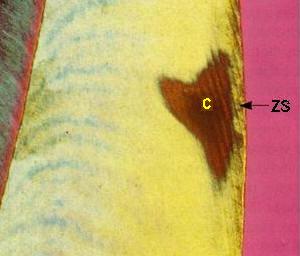

La figuras (izquierda)

muestran una sección longitudinal por desgaste, examinada

al microscopio con luz transmitida:

-

Zona superficial

(ZS): Es poco afectada porque recibe

minerales del cuerpo de la lesión

(1-2%

de porosidad)

-

Cuerpo de

la lesión (C):

Es el

área de mayor

desmineralización

(25-50%

de porosidad)

-

Zona

oscura

(ZD):

Desmineralización

(5-10%

de porosidad)

-

Zona

translúcida

(ZT):

No siempre está presente,

se encuentra en el avance

frontal

de la lesión,

ligeramente

más poroso

que el esmalte

sano,

la pérdida

de minerales

es del 1%